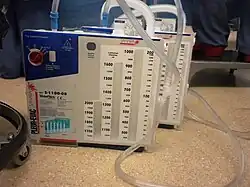

Een iatrogene pneumothorax is een pneumothorax veroorzaakt door een medische ingreep. Dit omvat zowel bedoelde als onbedoelde pneumothoraxen. Vroeger liet men weleens bewust een pneumothorax ontstaan om verschillende ziektes te behandelen, bijvoorbeeld tuberculose. Men dacht dat de tuberculose beter genas door het laten platvallen van een stuk long en dit in contact te brengen met zuurstofrijke lucht. Deze behandeling is inmiddels achterhaald. Het gebeurt nu nog dat een chirurg bij een operatie de longen even laat ‘plat leggen’. Je kan ook zien dat veel patiënten na een hart of longoperatie één of meerdere thoraxdrains krijgen. Dit doet men om lucht en/of vloeistof uit de borstholte te zuigen.

Een kleine spontane pneumothorax behoeft geen behandeling mits het lek gedicht is en de patiënt geen last ondervindt van de pneumothorax. Soms wordt er eenmalig via een naald of katheter lucht weggezogen waarna men deze naald meteen verwijdert. Bij een grote pneumothorax zal men de patiënt willen opnemen (al was het alleen maar omdat het fataal kan zijn er aan de andere kant ook een te krijgen, wat slechts in uitzonderlijke gevallen gebeurt) en zal men de pneumothorax via een thoraxdrain op waterslot onder een lichte onderdruk houden om de long weer te ontplooien. Lukt dit, blijft de patiënt enige dagen stabiel en vooral, als er geen luchtlek meer is, dan kan de drain weer worden verwijderd en mag de patiënt naar huis.